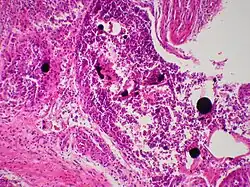

| Cutaneous mercury granuloma is a rare disorder caused by the introduction of elemental Hg into skin. | |

Mercury granulomas is the result of mercury exposure, a skin condition characterized by foreign-body giant cell reaction.[1]: 46